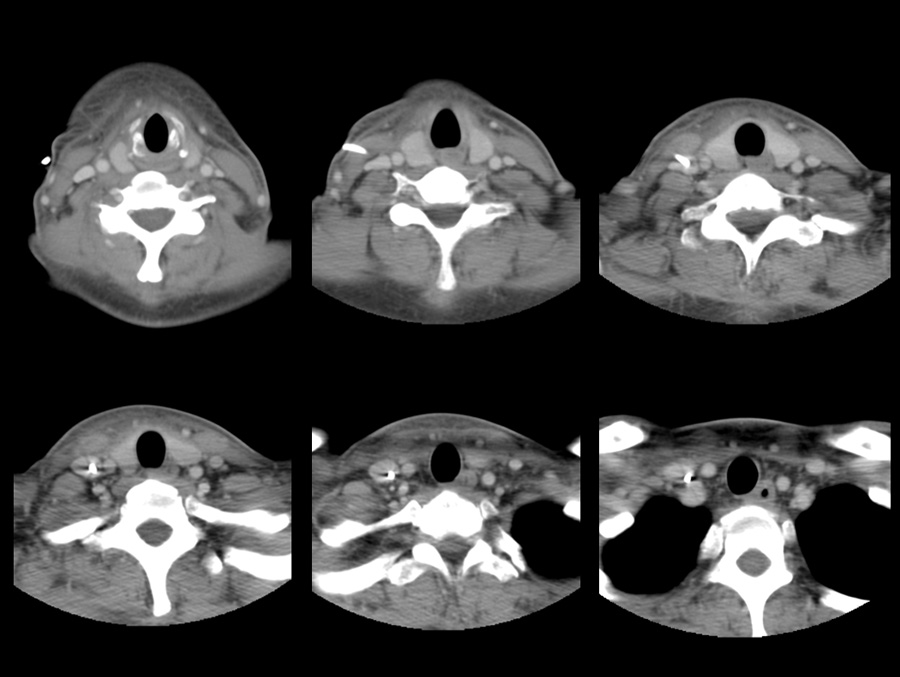

No.113症例3:40代 女性

半年前に急性骨髄性白血病と診断

化学療法の後、1ヶ月前に臍帯血移植後

微熱が2週間持続するため胸腹部CTを施行したが、原因ははっきりしなかった

(撮像範囲の頸部のみ比較画像を提示する)

翌日、頸部の腫脹・軽度圧痛を自覚

精査目的で再度頸部CTが依頼された

頸部CT

前日のCT(撮像範囲内で最も頭側の画像から提示)